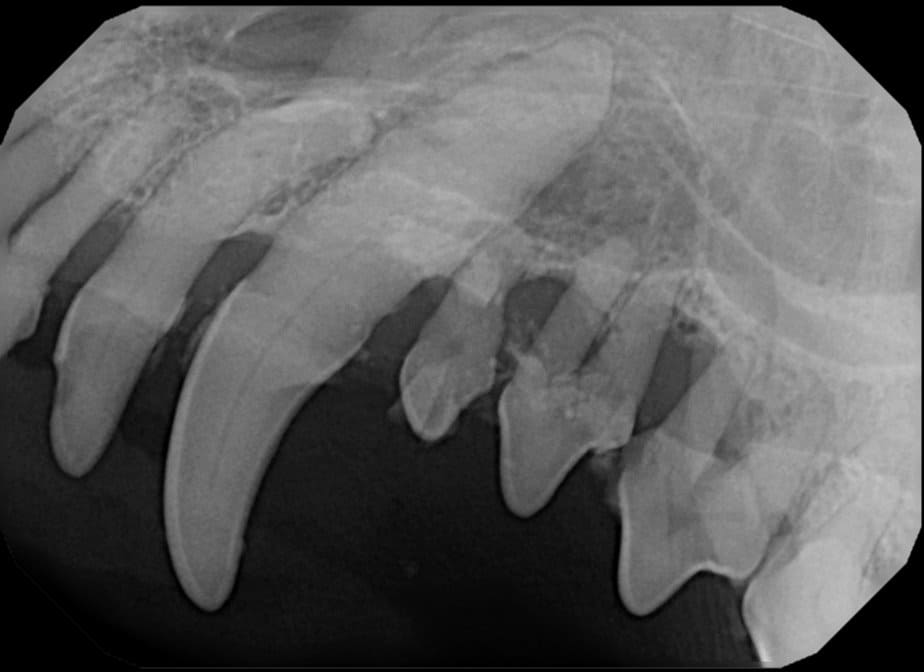

The Center now provides advanced imaging via cone beam CT. Cone beam CT is excellent for visualization of bony structures of the skull, nasal cavity, teeth, and ears. Cone beam CT is especially helpful for diagnosing dental disease and evaluation of jaw fractures. It can also be useful for evaluating the sinuses and tympanic bulla. Cone beam CT can be used in conjunction with nasal biopsy and culture to evaluate nasal discharge whether chronic or acute.

Periodontal disease is extremely common in dogs and cats. Over 80% of dogs and cats over two years of age have some degree of periodontal disease. Periodontal disease is best prevented by yearly professional dental cleanings starting at two years of age and at home brushing at least three times weekly. Brushing should begin at a very early age to allow your new pet to get used to regular brushing. In severe cases of infection or periodontal disease, the teeth may need to be surgically extracted. Extractions should always involve x-rays of the tooth first, as many teeth have multiple roots or may be diseased below where the eye can see. Extracting larger teeth in animals requires oral surgery, equivalent to removing wisdom teeth in people. It is vital that all of the tooth and roots be removed for the periodontal infection to resolve. In cases of important teeth with mild to moderate periodontal disease, multiple periodontal treatments can be offered to help save these teeth.